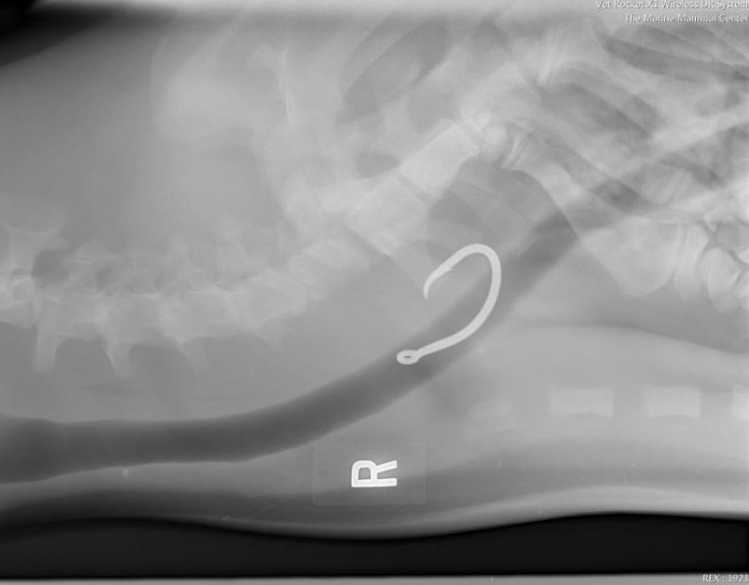

One of the threats facing Hawaiian monk seals is accidental ingestion of fishing hooks, a fatal mistake for a hungry seal. With the donated Vet Rocket X1, our animal care staff will be able to determine right there on the beach whether an ailing monk seal has ingested a hook and its location inside the animal's body.

If a fishing hook is found via X-ray, the seal can be rushed to The Marine Mammal Center’s Ke Kai Ola hospital for surgery.

Earlier this year, Dr. Johnson tested a prototype of the Vet Rocket X1 on KE-18, an adult Hawaiian monk seal currently being housed at Long Marine Laboratory in Santa Cruz, California. The machine was able to detect hooks placed near the seal’s neck, upper body and abdomen.